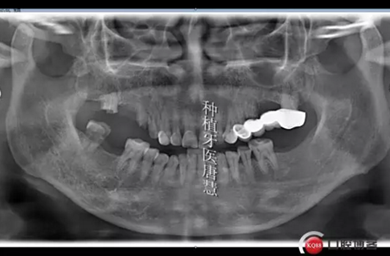

患者劉xx,女,55歲,右上后牙區(qū)殘根,來診咨詢種植。

查見14、15、17殘根狀,松動(dòng)II°,叩診不適,根尖區(qū)有大面積陰影;16、47缺失,48大面積齲壞

治療計(jì)劃:拔除14、15、17、48,種植14、16、17、固定修復(fù),47種植修復(fù),患者要求先種植14、16兩顆